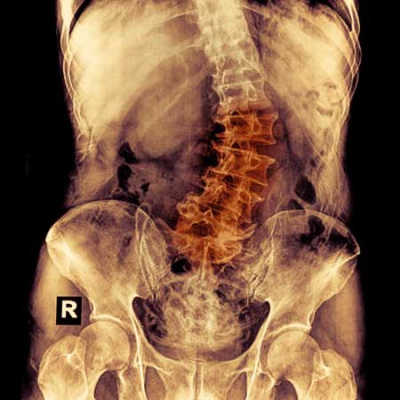

USPSTF Recommendation: Screening for Adolescent Idiopathic Scoliosis

Interview with Alex R Kemper, MD, MPH, MS, Task Force member and co-author of Screening for Adolescent Idiopathic Scoliosis: US Preventive Services Task Force Recommendation Statement